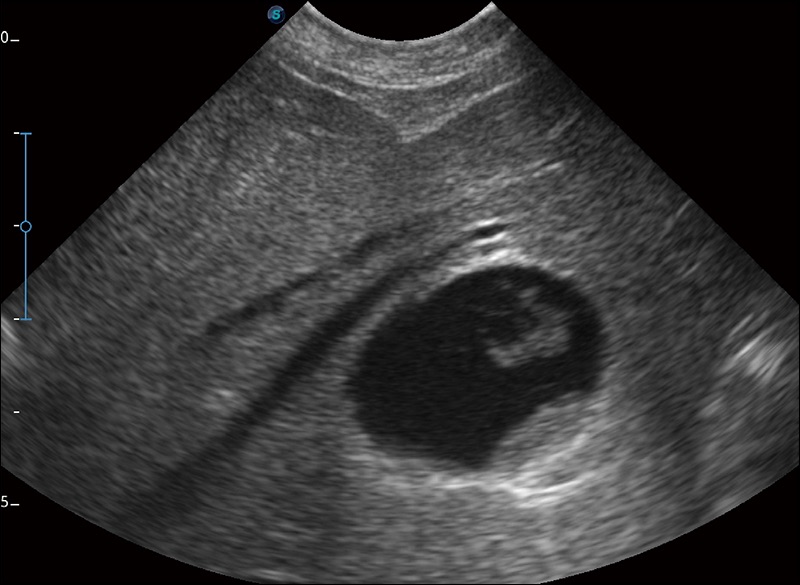

實(shí)時(shí)寬景成像

可實(shí)時(shí)觀察感興趣區(qū)域和病變位置